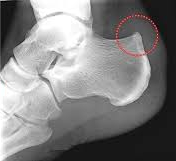

사람에 따라서는

힘줄이 부착된 뼈를

잡아당기면서

뼈가 점점 자라나기도 합니다.

이를

[하글런드 변형]Haglund's deformity

이라고 합니다.

뼈에 가시가 돋는 모양이라

뼈 골, 가시 극

[골극]**이라고도 부릅니다.